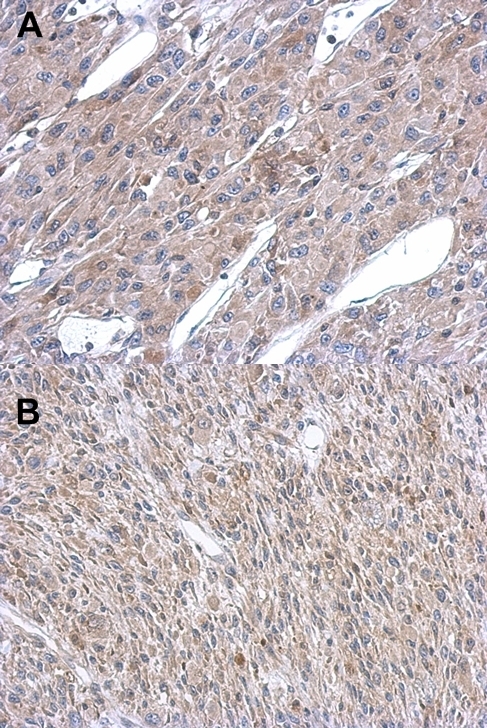

- A:Immunohistochemical analysis of paraffin-embedded U87 xenograft, using ASL antibody at 1: 500 dilution. B:Immunohistochemical analysis of paraffin-embedded C2C12 xenograft, using ASL antibody at 1: 500 dilution.